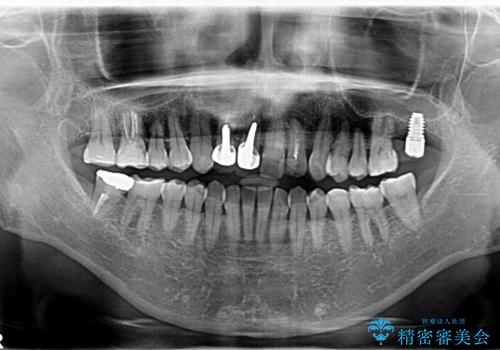

左上は他院でインプラントを入れたが、クラウンの脱離を繰り返して、仮歯に戻したあともうそれでいいと言われたとのことでした。

インプラントの製造会社は当院で使っているものと異なったため、ドライバー等購入し対応しました。

全体的にプラスチックで治療してあり、劣化していたのと、また、右上6番は根の治療がされていましたがプラスチックで埋めてあるだけで中を見たところ残念ながら割れていました。その歯は抜歯し⑤6⑦ブリッジにしています。

右下のクラウンレングスニングについては以下に載せています。